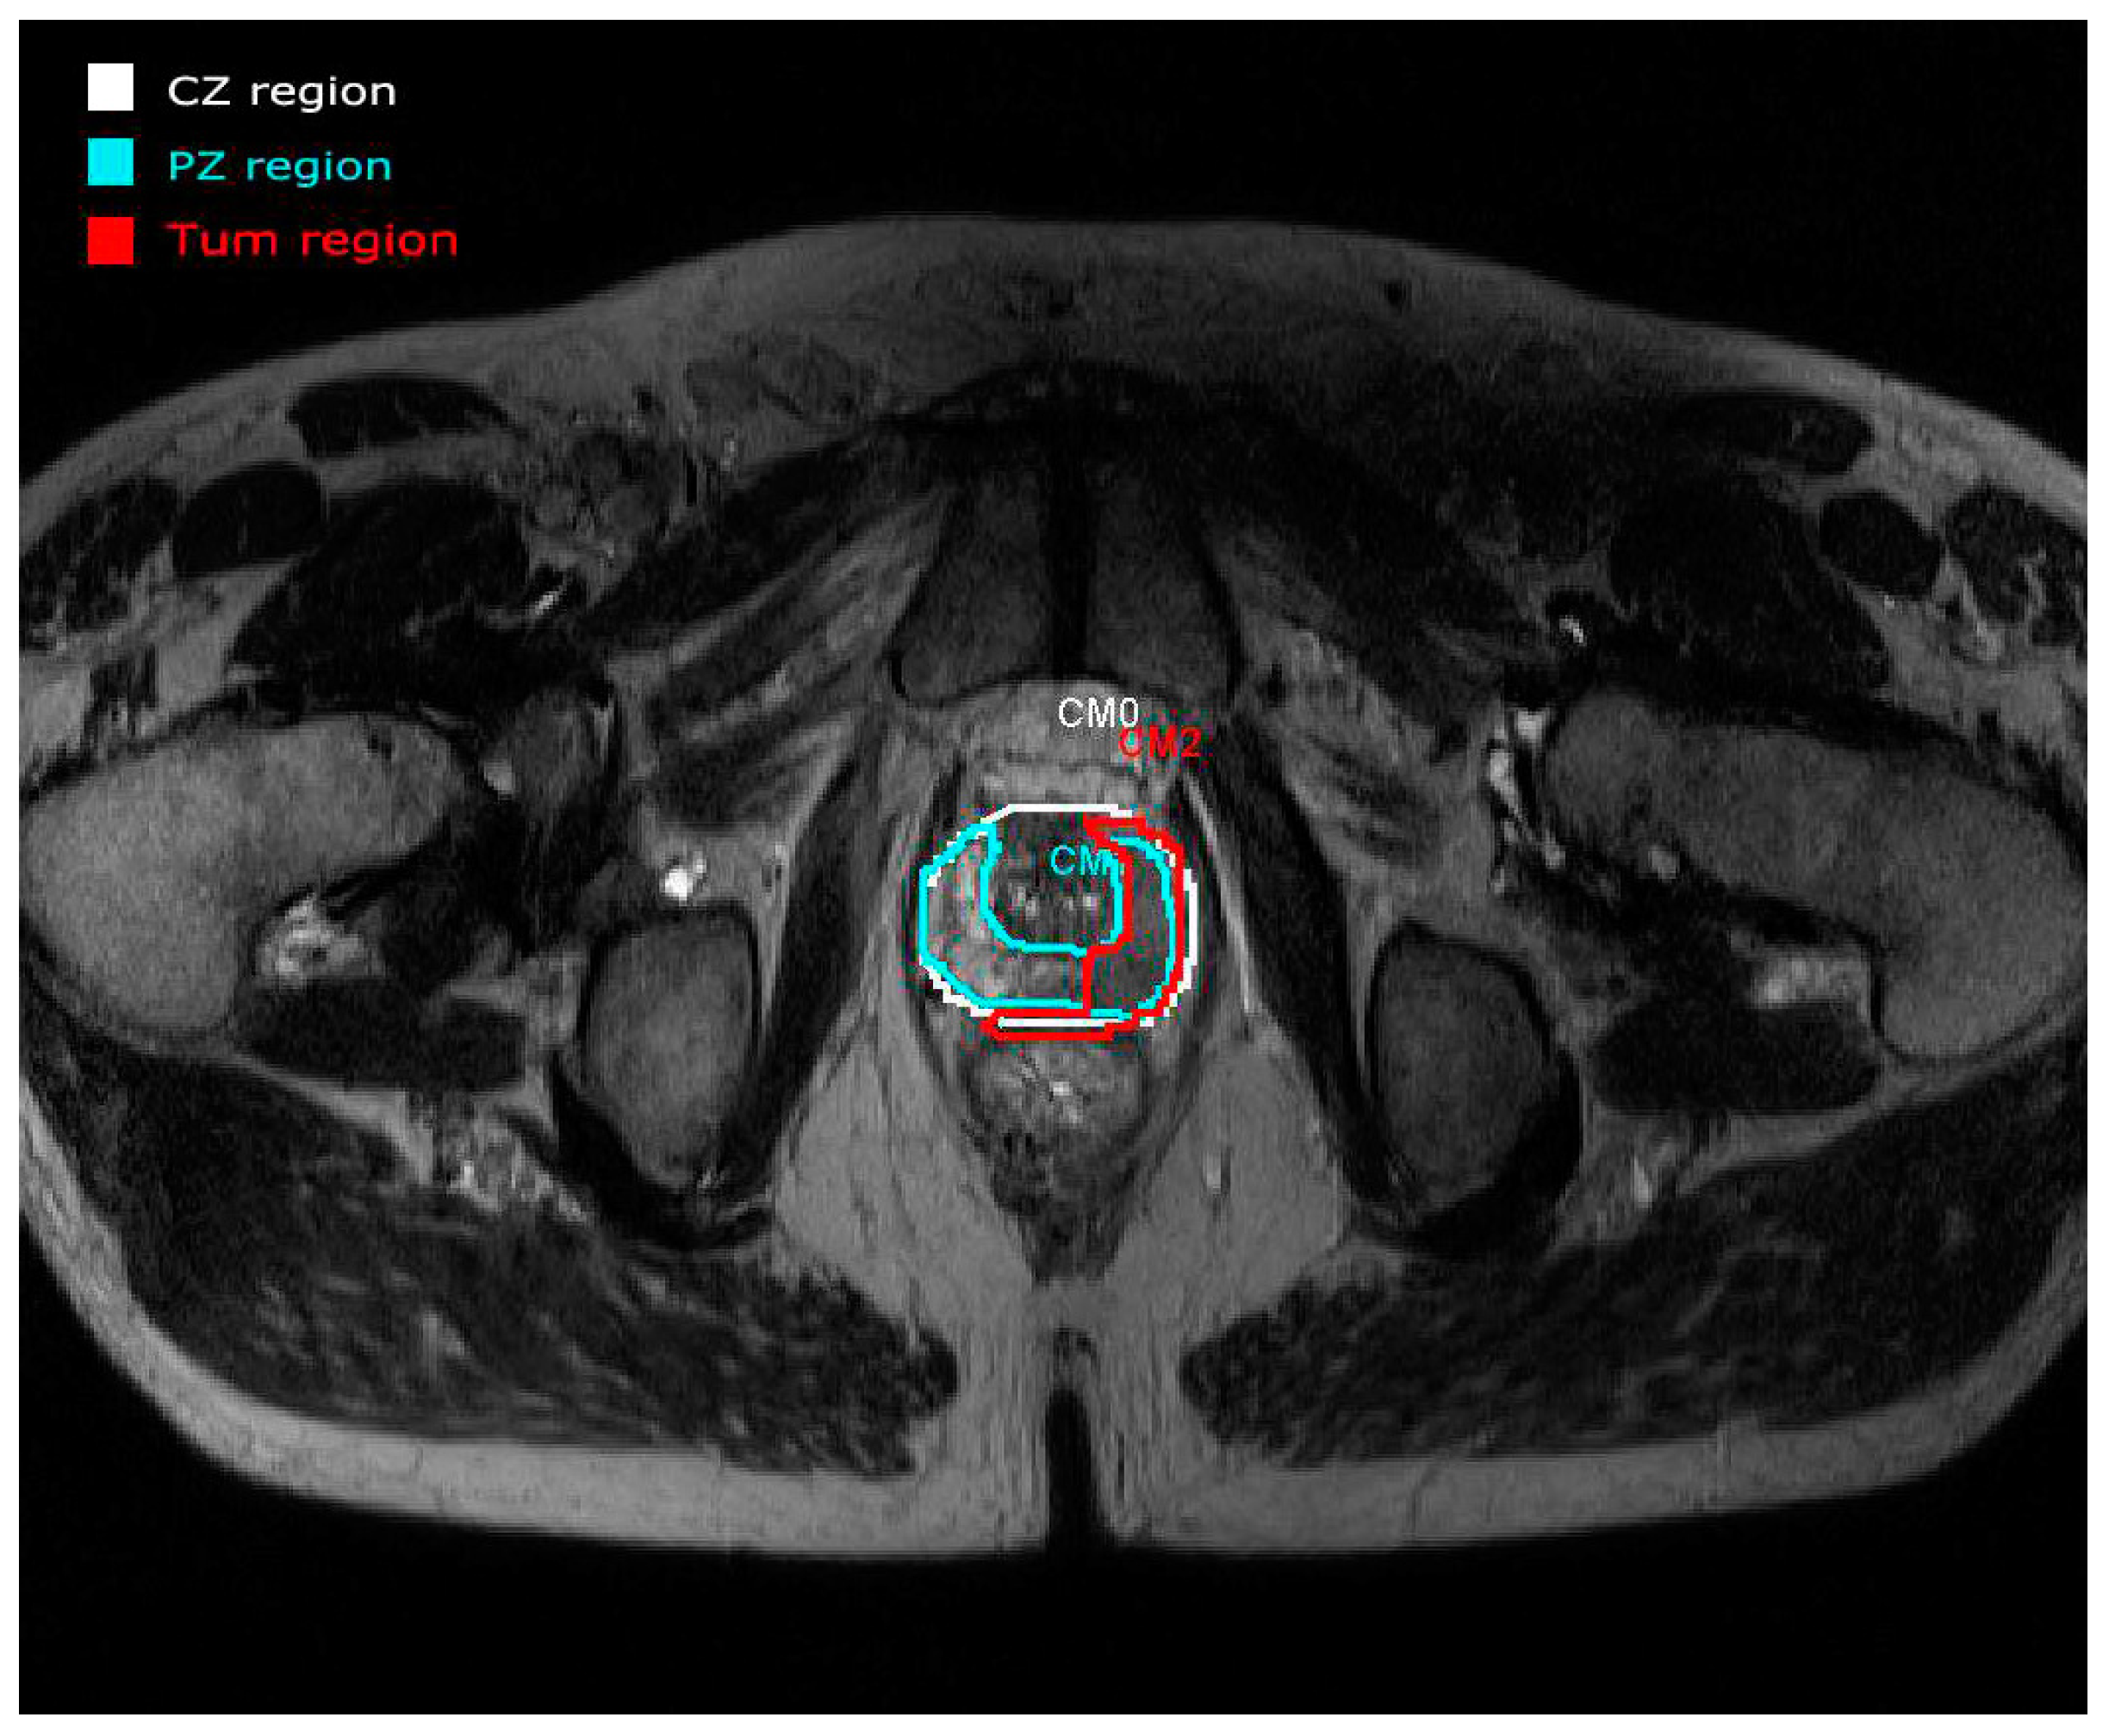

The PZ represents up to 70% of a normal prostate gland and around 75% of prostate cancers originate in this zone. The CZ represents about 25% of a normal healthy prostate gland in young adults. Even though the frequency of cancers originating here is much lower, they tend to be of the more aggressive type [14]. An example of a real study case provided by the panel visualization of the prostate tool [11] is depicted in Figure 2. All the overlays are annotated with manual drawings made by radiologists. Each region is represented by different colors (CZ in white and PZ in blue) focusing on a tumor area represented in red (Tum). This example shows the importance of making annotations in regions of interest. In this case, a manual segmentation is validated by experts.

Figure 2. An example of the anatomy (T2WI) panel visualization of the tool developed in [11] with the ROIs annotated by radiologists.